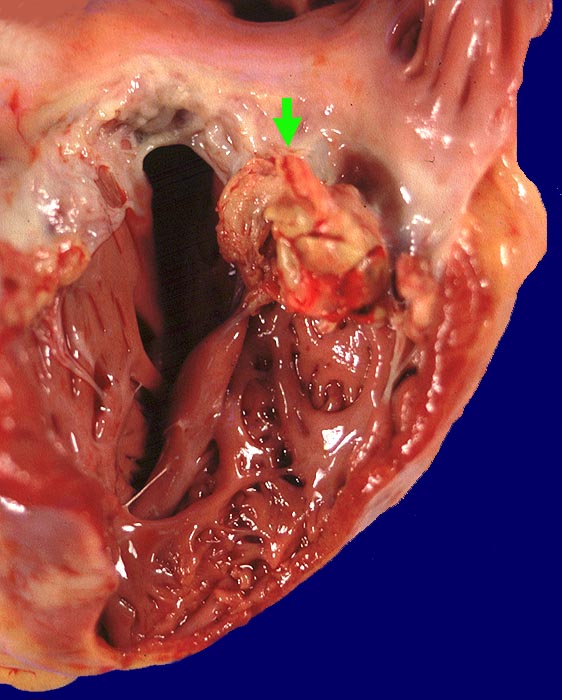

PathoPic – image database / PathoPic ID 973 - Polypöse Endokarditis

Polypöse Endokarditis

Trikuspidalklappe

Polypöse Vegetation auf der ansonsten intakten Trikuspidalklappe.

Kleine Vegetation auf der Mitralklappe. Nachweis von gram positiven Kokken. Septisch embolische Lungeninfarkte mit Nachweis gram positiver Kokken. Floride chronische Osteomyelitis bei Spritzenabszess am Unterschenkel.

Infektiöse Endokarditis bei iv Drogenabusus. Chronische Hepatitis C.